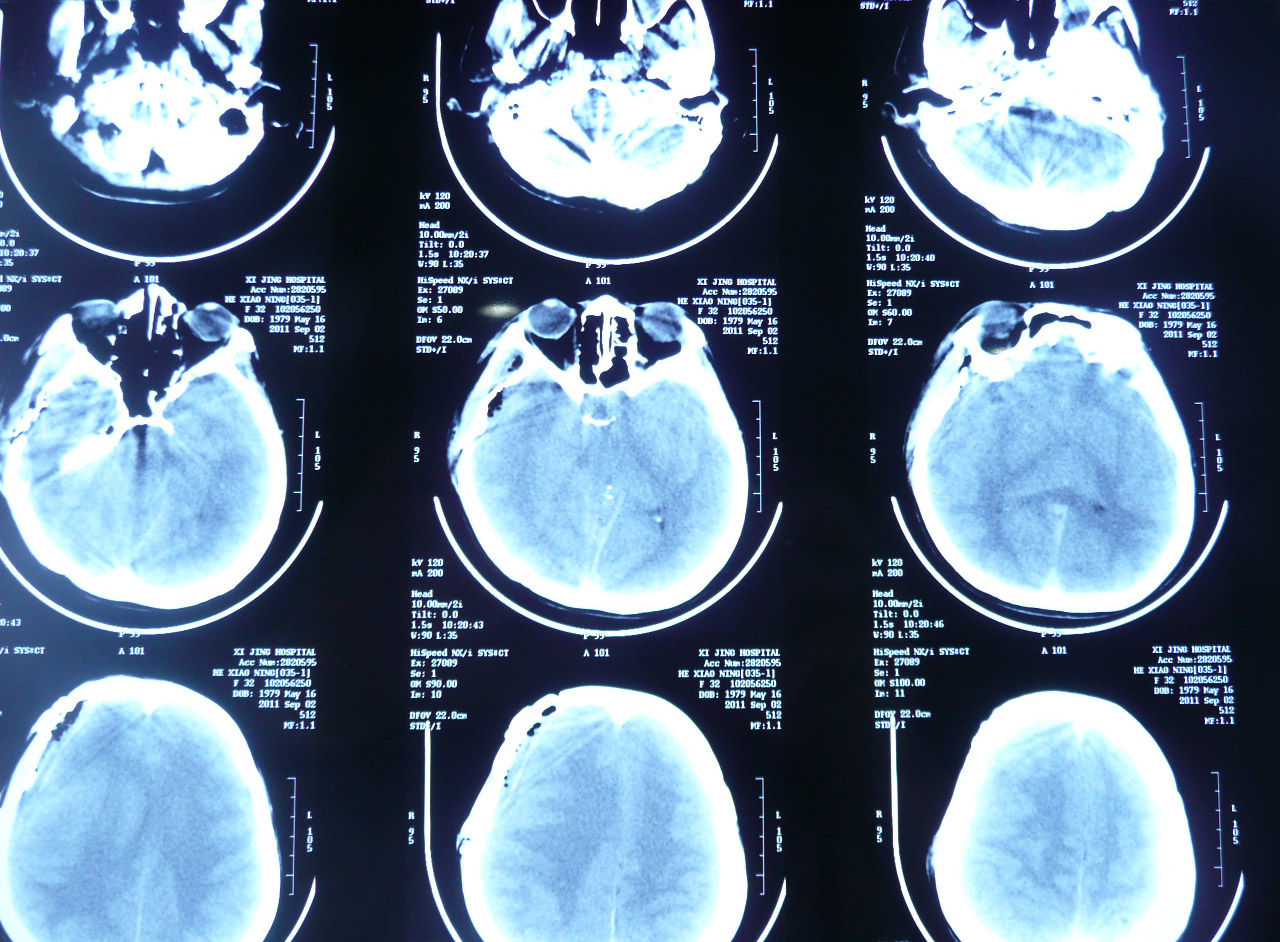

西京医院鞍区囊肿的手术治疗(实例)

图片尺寸766x566